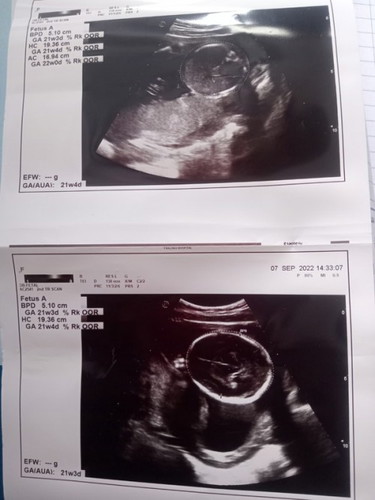

เมื่อวานไปหาหมอไปซาวมาค่ะ หมอบอกว่ากึ่งชายกึ่งหญิง เราเห็นเป็นกลีบน้อง แต่หมอบอกให้รอลุ้นอีกทีตอนคลอด เราอยากได้ลูกสาวมากๆค่ะ แต่คนเขาก็ชอบทักว่าไปลูกสาวนั้นล้ะ หมอไม่ได้ปริ้นภาพตอนซาวเพศน้อง เสียดายมากอยากให้ทุกคนช่วยดู แต่พี่ๆน้องๆคนอื่นบอกว่าสะดือจุ๋นน่าจะได้ผญ.#ขอบคุณสำหรับคำตอบค่ะ #ท้องแรกคะ #ทายเพศลูกในครรภ์